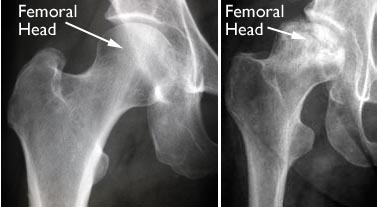

(Left) An x-ray of a healthy hip joint. (Right) In this x-ray, the osteonecrosis has progressed to collapse of the femoral head.

X-rays. These scans create pictures of dense structures, like bone. X-rays are used to determine whether the bone in the femoral head has collapsed and to what degree.

Osteonecrosis of the hip develops when the blood supply to the femoral head is disrupted. Without adequate nourishment, the bone in the head of the femur dies and gradually collapses. As a result, the articular cartilage covering the hip bones also collapses, leading to disabling arthritis.